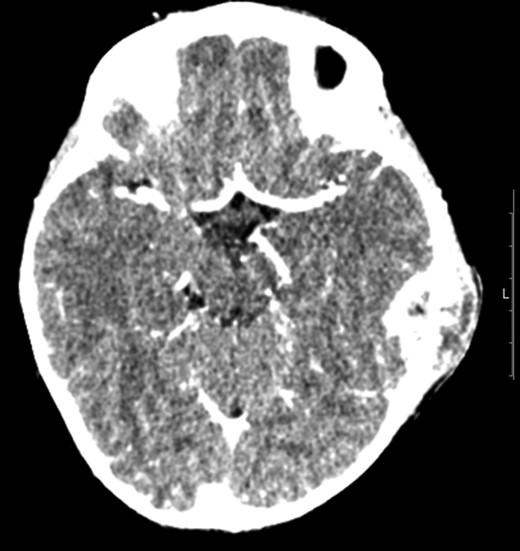

Patient underwent MRI imaging (Day 6 post drainage) which showed near resolution of the epidural and extracranial collection (Fig. 3). Upon review of images it was decided that no further surgical input was necessary, and the patient was discharged with follow up planned within 2 weeks.

Transverse magnetic resonance image 3 months post op showing some residual inflammation within the post-surgical mastoid cavity (white asterisk) and resolution of collection.